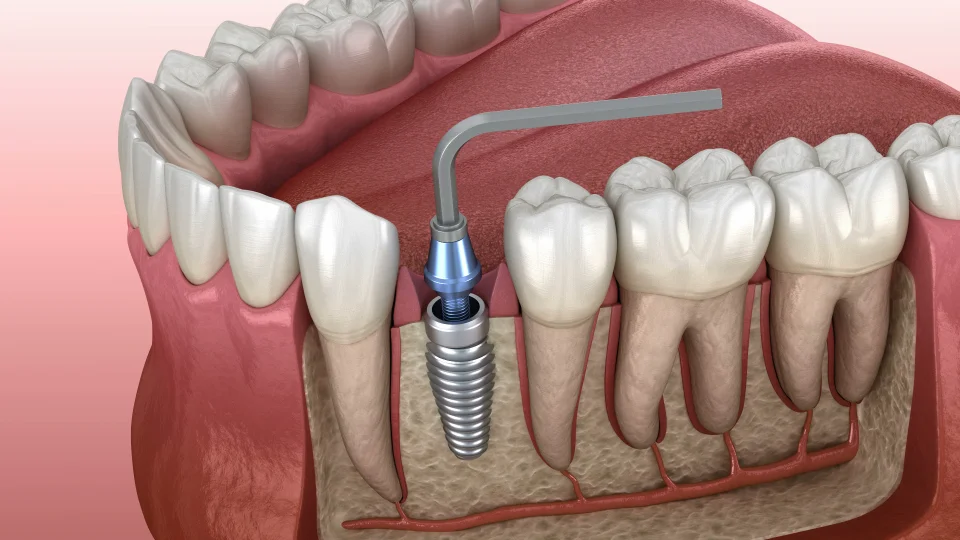

In general, one implant is used per missing tooth. For molars or teeth with multiple roots, a wider or specially designed implant may be necessary to provide extra support.